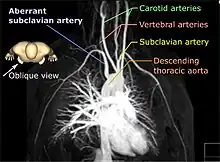

A 3D rendered magnetic resonance angiography, shown in an oblique projection in order to distinguish the aberrant subclavian artery